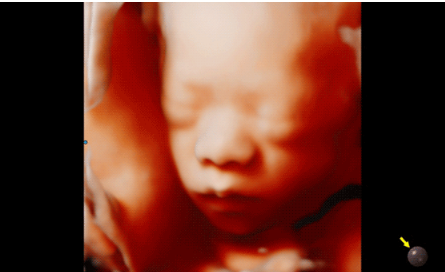

3D/4D成像方面,Hera i 10通過結(jié)合先進(jìn)的圖像渲染技術(shù),著重加強(qiáng)了邊緣和小結(jié)構(gòu)的可視化能力。